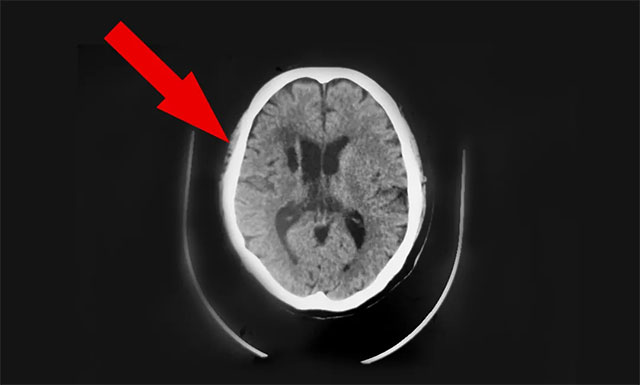

近期,因头晕不适感持续,前往上海某医院就诊检查。行头颅CT发现:1. 两侧半卵圆中心区及基底节区多发腔隙性脑梗塞;2. 左小脑及右侧基底节区斑片软化灶;门诊拟以“颈内动脉狭窄、脑梗死”收入。治疗一个月后无明显改善。为求进一步治疗,9月中旬胡夫人陪同患者胡某慕名转往上海蓝十字脑科医院,由6B神经外科潘仁龙主任接诊。

在潘仁龙、吴志群及黄秀夫三位医生会诊下,基于患者近半个月主诉有头晕,偶有行走不稳,头晕症状明显,次数较前明显增加。9月16日CT头颅CTA+CTP 示病患右侧大脑中动脉M1段、左侧大脑后动脉多处狭窄,右侧大脑中动脉中央、远端分支明显稀疏、减少等;考虑心脏支架术后状态,基础性疾病较多,颅内多发血管性狭窄,行血管搭桥手术风险较高,建议行颞肌贴敷术,以改善患者病情,提高患者生活质量,建议尽早手术治疗。

▲ 手术前